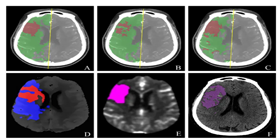

• 系统截图